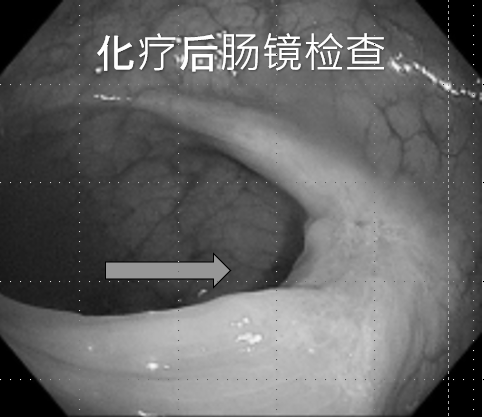

01/

患者秦先生,因“大便带血3月余”诊断“中位直肠中分化腺癌cT4aN1M0 IIIB期”,经多学科MDT讨论,根据NCCN、CSCO指南,予CAPEOX方案新辅助化疗5周期,化疗效果良好,肿瘤 “完全临床缓解(cCR)”。

行腹腔镜直肠癌根治术治疗。

▲术后病理:

●肿瘤位置:瘤床不明显;未见脉管内癌栓及神经侵犯;切缘阴性;未见淋巴结转移;

●TRG评分:0(无肿瘤细胞残留)。病理学完全缓解ypT0N0cM0,患者术后恢复良好。